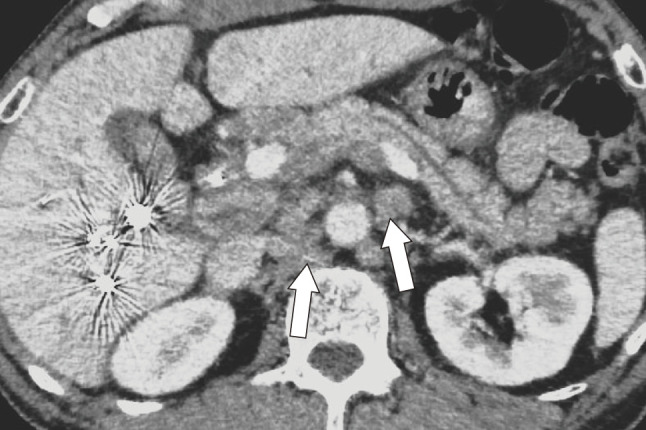

Case presentation: A 70-year-old man was diagnosed with hilar CC (cT3N1M0, Stage III C) based on biopsy of the common bile duct stenosis and computed tomography (CT) and magnetic resonance cholangiopancreatography scans. Initially, a right lobe hepatectomy and subtotal stomach-preserving pancreatoduodenectomy were planned. However, there were concerns about an insufficient functional remnant liver volume. Trans-ileocolic portal embolization of the right portal vein branch was performed. On a preoperative CT scan 1 month later for liver volumetry, swelling of the para-aortic lymph nodes was observed, which was judged as distant metastasis, and radical resection could not be performed. After 8 courses of durvalumab plus gemcitabine and cisplatin therapy, vanishing fluorodeoxyglucose accumulation in the para-aortic lymph nodes was observed on positron emission tomography-CT. The possibility of resection was reevaluated, and a right lobe hepatectomy and extrahepatic biliary reconstruction were performed as conversion surgeries. Histological examination confirmed the absence of residual tumors or lymph node metastases. Ten months after surgery, the patient was free of recurrence.